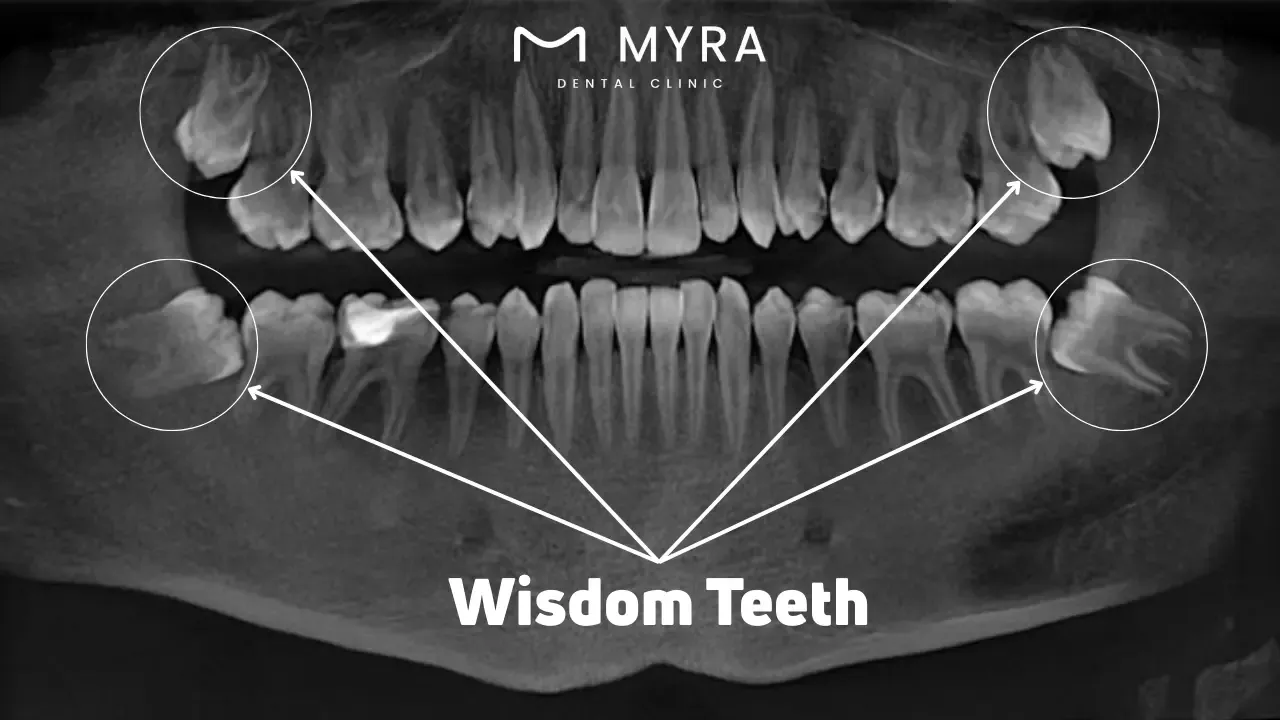

Wisdom teeth are the last set to emerge between 17 and 25. Some people have no trouble with their wisdom teeth, but others experience pain, infection, and wisdom teeth getting stuck. The issues necessitate medical intervention, ranging from medication to surgical extraction. Understanding the symptoms, treatment options, causes, and research surrounding wisdom teeth helps manage and prevent complications effectively.

How Common are Wisdom Teeth?

Wisdom teeth are common, growing between 17 and 25. Individuals commonly have between one and four wisdom teeth, but the number of people who have them varies greatly. Studies indicate that anywhere from 5% to 37% of adults worldwide never develop wisdom teeth. The variation is attributed to several factors, including genetics and evolutionary changes in human jaw size and dietary habits. A study published in the Dental Research Journal found that between 5% and 37% of the population have congenitally missing wisdom teeth, a condition known as the absence of wisdom teeth at birth.

Several risk factors influence the growth of wisdom teeth. The primary determinant is heredity, with family patterns determining whether these teeth are present. Environmental factors, including diet and chewing habits, affect the development of wisdom teeth. A modern diet that requires less chewing leads to smaller jaw sizes, contributing to higher impaction rates. Diseases and trauma disrupt the late development of wisdom teeth, preventing their growth altogether. Impacted wisdom teeth, which grow at an angle and become trapped beneath the gum line, pose further risks such as oral infections, tooth decay, pain, and other health issues.